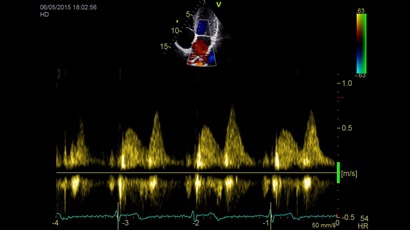

• Передовые технологии, такие как 4D чреспищеводная эхокардиография, ЭКГ, стресс-эхо, внутрисердечная ультразвуковая эхокардиография, тканевый доплер и другие.

Тканевой допплер:

Да

Направленный энергетический допплер:

Энергетический допплер:

Высокочастотный импульсный допплер:

Цветовой допплер:

Постоянно-волновой допплер:

Импульсно-волновой допплер:

• Режимы: 4D, 2D (B-режим), цветной допплеровский режим, режим энергетического допплера, M-режим, цветной M-режим, спектральные режимы импульсно-волнового допплера (PW) и непрерывно-волнового допплера (CW), визуализация скорости движения тканей.